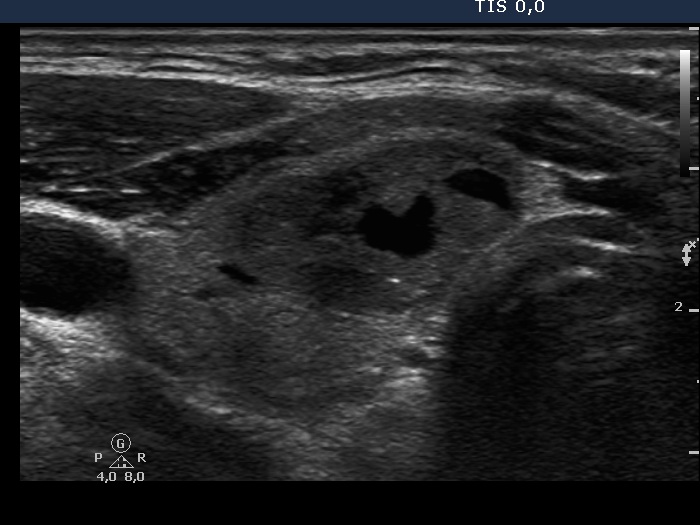

Benign hyperplastic nodules (histological diagnosis) - case cons 024 |

The larger lesion has a solitary bright figure which shape stands for a comet-tail artifact.

There are pale lines and granules within the nodule - these figures correspond to a connective tissue. The three granules are probably also presentations of a connective tissue.